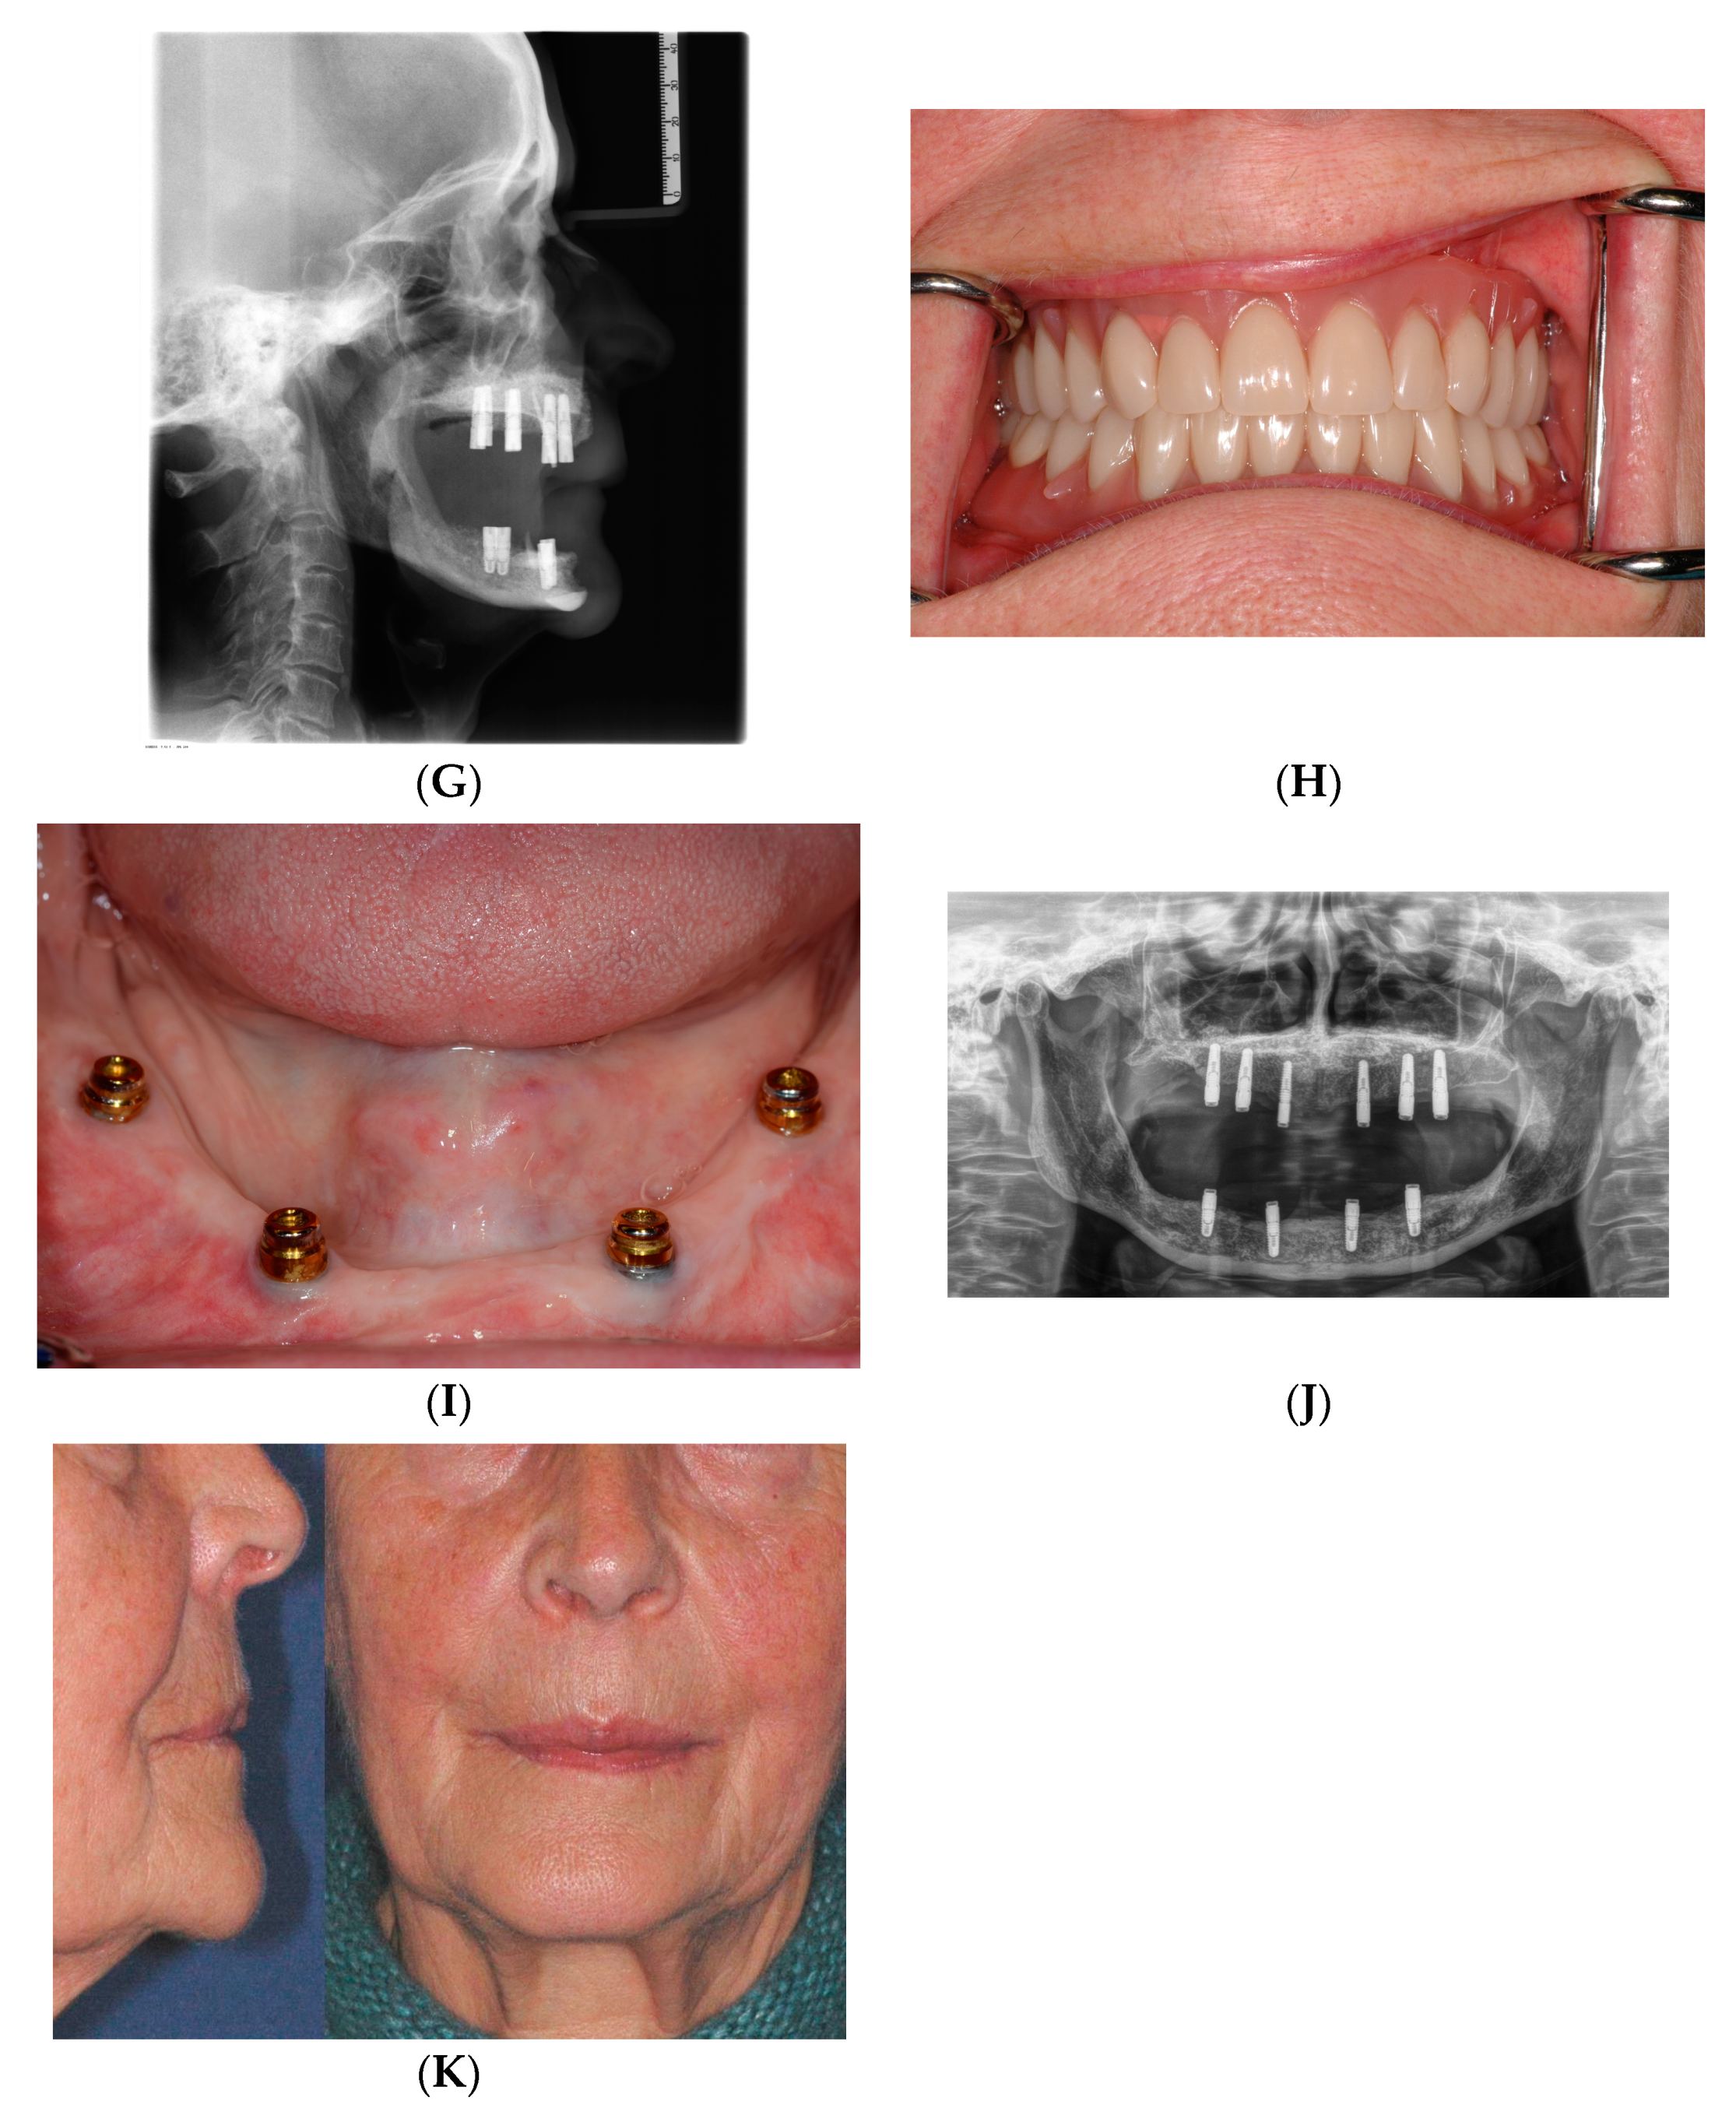

5. Vertical Ridge Augmentation—Sandwich versus Onlay Grafting